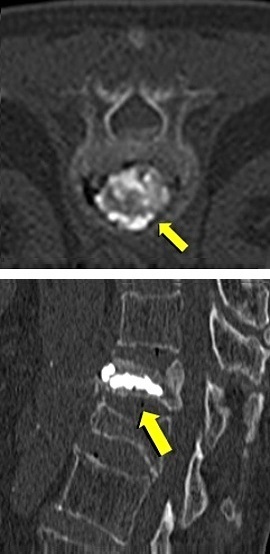

◆圧迫骨折/骨転移に対する経皮的椎体形成術(PVP)

経皮的椎体形成術(骨セメント)の実際

局所麻酔下で皮膚から椎体に針を刺し、骨セメントを注入することにより、椎体を内部

から固定する方法です。骨粗鬆症による圧迫骨折で痛みを伴うもの、椎体の腫瘍(癌の

転移など)による痛みを伴うものが適応となります。古い圧迫骨折による亀背や側弯が

あっても、痛みがないものや、症状のないものは治療の適応となりません。症状が軽度

であっても歩行時、起立時に痛みがあり、画像診断で治癒していない圧迫骨折がある場

合は治療の適応となります。術前の画像診断にはMRI検査が重要で、病的骨折、骨粗鬆

症性骨折、治癒していない骨折の診断に不可欠です。

治 療 前 セメント注入中 治 療 後